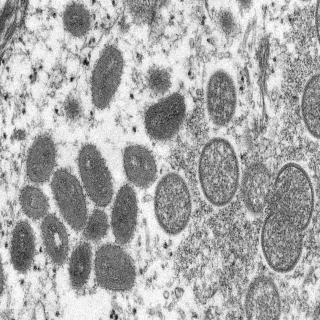

Mpox virions

Electron microscope image of mpox virions from a human skin sample. On the left are mature, oval-shaped virus particles, and on the right are the crescents, and spherical particles of immature virions.

Like all poxviruses, mpox virions are large, enveloped and “brick-shaped." Encapsulated within each virion is a core containing a linear, double-stranded DNA genome and enzymes required for virus uncoating and replication. At the onset of infection, poxvirus particles attach to the host cell membrane through various viral-host protein interactions. Notably, while other mammalian DNA viruses replicate in the nucleus, poxviruses replicate in the cytoplasm in small compartments known as 'factories', formed from the host rough endoplasmic reticulum (ER). Though they come wielding their own transcriptional machinery, poxviruses rely on host ribosomes to translate mRNAs into the structural components of the virion, as well as proteins that dismantle the factory’s ER membrane. Such dismantling gives rise to small, membranous crescents that grow to encapsulate the genome of assembling virions. Progeny poxviruses are decorated with additional membranes from the trans-Golgi network before exiting the cell via plasma membrane fusion.